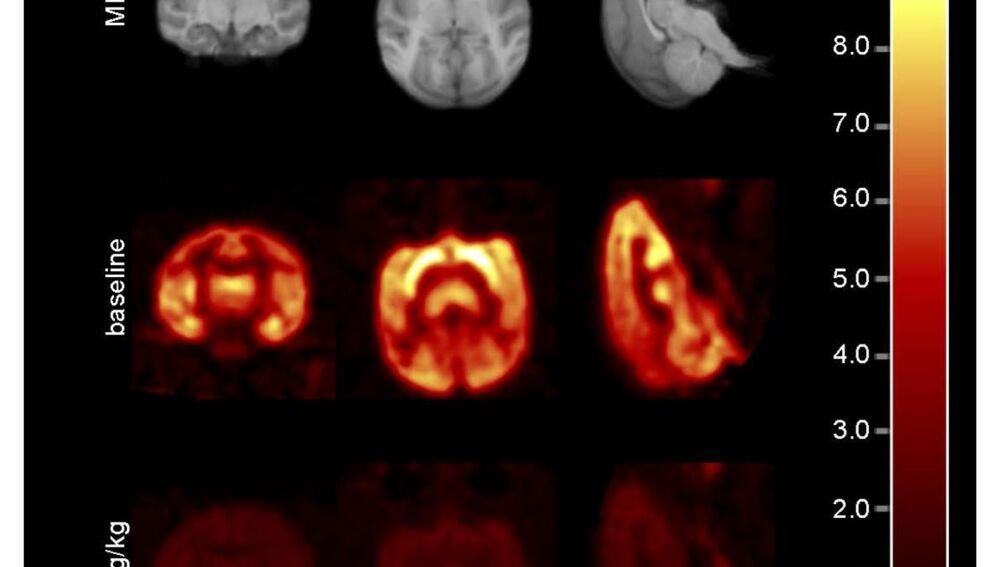

Imágenes de resonancia magnética y de una tomografía de un mono antes y después de recibir el BMS-984923 | EFE/J. Spurrier Science Translational Medicine

Los investigadores han comprobado por primera vez, gracias a las imágenes de resonancias magnéticas y tomografías, cómo el fármaco actuaba con eficacia sobre los receptores mGluR5 del cerebro de los monos y ratones, sin causar efectos secundarios.